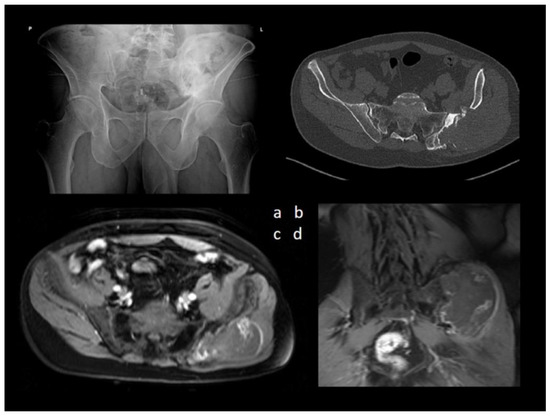

A 47-year-old man presented to our outpatient department with a growing, painful tumor in the region of the left iliac bone. He sustained bone graft harvesting from the iliac crest for spinal fusion due to scoliosis 29 years ago, and he had not had any problems in the past. Therefore, no imaging method was available for comparison. He stated he did not have any history of trauma, and he had observed the tumor for one year. The patient had already undergone an inconclusive diagnostic checkup at a different hospital, with an open biopsy only yielding nonspecific findings of tissue necrosis. Imaging methods were used (Figure 1).

The combination of aggressive bone destruction, lesion extending into the pelvis, and a non-aggressive sclerotic margin with a narrow zone of reactive osteosclerosis were considered controversial. A significant portion of the lesion infiltrated the gluteal muscles, displaying subtotal central necrosis and a thin viable (enhancing) rim preserved in the periphery. Calcification of an unusual morphology was visible in the center of the lesion. Bone destruction associated with soft tissue mass and an irregular tumor shape suggested a malignant lesion. Ultrasound assessment and ultrasound-guided needle biopsy followed (Figure 2).

Figure 1. (a) Anteroposterior radiography of the pelvis revealed an extensive mixed lytic and sclerotic lesion of the left iliac bone. (b) Axial CT image of the lesion and MRI T1-weighted fat-suppressed contrast-enhanced sequences of the pelvis—(c) axial view and (d) coronal view demonstrated a large, aggressive lesion causing extensive osteolysis of the left iliac bone.